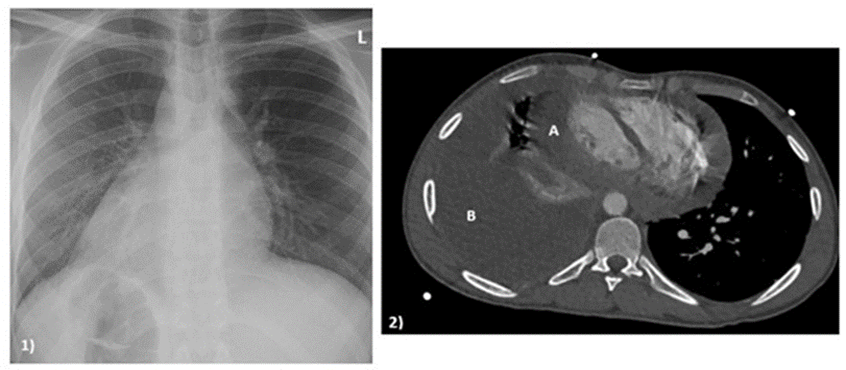

We present a 23-year-old patient with infectious pericarditis due to tuberculosis, with concomitant situs inversus totalis. He is from Eritrea and had been living in Germany for one and a half years. The patient stated that he had never been ill before and lived in a stable environment. His medical history included pain in the flank region for two weeks, as well as respiratory-dependent chest pain and cough with whitish sputum. The patient was referred to our clinic with polyserositis, right-sided pleural effusion, and a circular pericardial effusion of up to 1.7 cm end-diastolic (Figure 1).

Figure 1: preoperative diagnostics. 1) X-ray in october 2025; 2) Computertomography in december 2025; A: thickened pericardium with effusion component; B: massive pleural effusion.